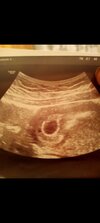

Zrobiłaś betę oraz jest wzrost po 48h? Wg OM jesteś w ponad 6tc. O której masz wizytę u lekarza?24 kwietnia powinnam dostać okresu 27 wykonałam dwa testy były dwie sale kreski

Marzec? Na pewno? Ja miałam OM 24.03 i jestem w 6+5 tc, do zapłodnienia doszlo koło 8-9 kwiet

Beta też nie wyjdzie bo przy pustym jajeczku też idzie do góryO 15.

Mnie to daje do myślenia że jeszcze jest szansza że jak robiłam testy to były słabe kreski30-32 dni